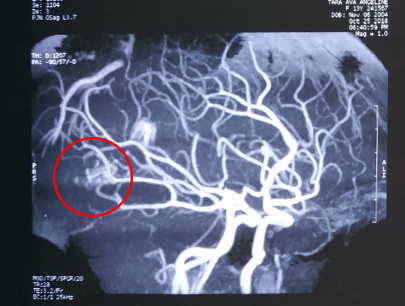

AVM (Arterivenous Malformation)

Kelainan pembuluh darah otak non-stroke

SEBELUM

SESUDAH

(Perempuan, 14 tahun)

Diagnosis: Malformasi Arteri-Vena Oksipital Kanan

Sebelum Gamma Knife

• Nyeri Kepala

3 bulan Setelah Gamma Knife

• Kebutaan menetap

• Penonjolan mata kiri berkurang

Diameter Nidus: 1.5 cm

Nidus tidak ada